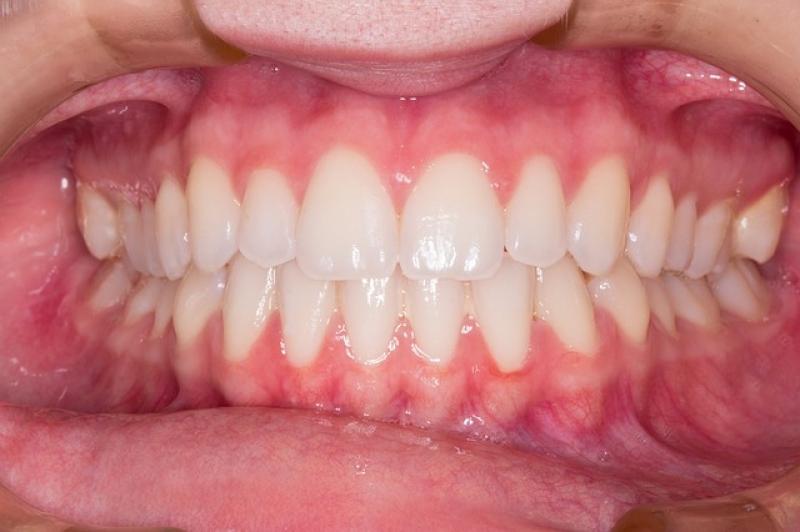

Jednak nie wszystko stracone! Kluczem do sukcesu pozostaje wczesna interwencja oraz nauka odpowiednich nawyków higienicznych. Miękka szczoteczka oraz technika „wymiatania” mogą zdziałać prawdziwe cuda. A jeśli mycie zębów staje się bolesne, warto zainwestować w specjalne pasty, które łagodzą nadwrażliwość. Zdarzyło się Wam kiedykolwiek spojrzeć na reklamę idealnego uśmiechu i pomyśleć: „Chcę tak wyglądać!”? W takim razie czas udać się do dentysty i postawić na zdrowie dziąseł – bo piękne zęby to nie tylko kwestia estetyki, ale i fundament, na którym opiera się nasz uśmiech!

Na koniec warto podkreślić, że zdrowe zęby i dziąsła mają najwyższą wartość. Regularne wizyty u dentysty, zrównoważona dieta oraz odpowiednia higiena jamy ustnej mogą zagwarantować nam codzienny komfort. Pamiętajcie, dobrych nawyków nie można odkładać na później – nadwrażliwość zębów nie przypomina polskich kotletów schabowych, które mogą odczekać kilka dni w zamrażarce. Radźcie sobie z problemami natychmiast, zanim zamienią się w lawinę zmartwień. Uśmiechajcie się szeroko i z odwagą, ponieważ zdrowa jama ustna stanowi klucz do szczęśliwego życia!